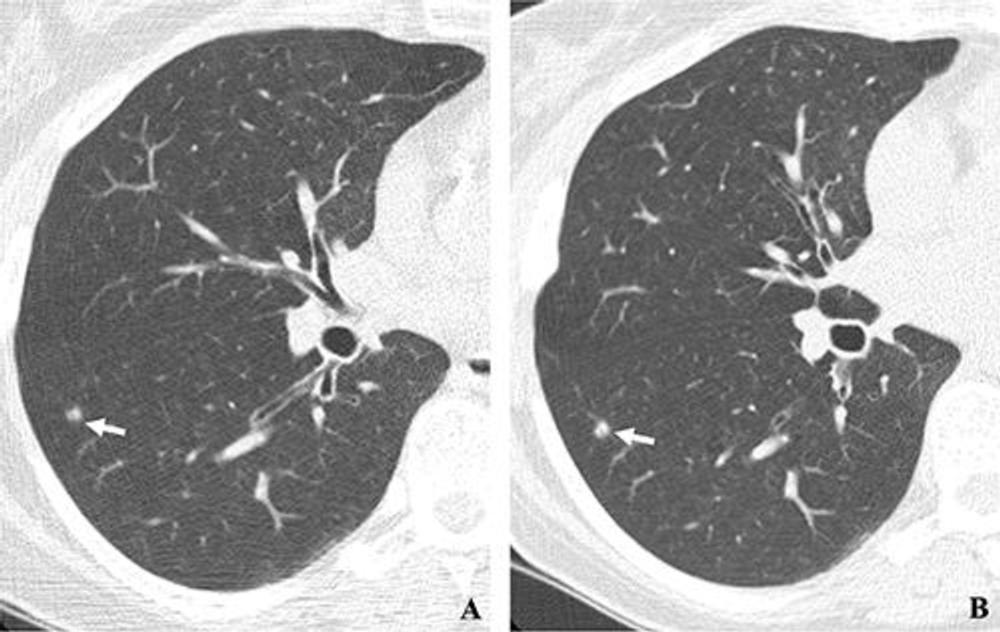

Figure 2. (A, B) Two annual repeat low-dose CT scans in a woman who was 60 years old at baseline enrollment in 1999. At baseline enrollment, she was currently smoking and had a 30-pack-year smoking history. No nodules were identified on baseline low-dose CT scans. On the sixth annual low-dose CT scan (B) , a right lower lobe solid nodule (arrow) measuring 4.5 mm in maximum diameter was identified. The nodule could be identified in retrospect on the prior annual CT scan (arrow in A), when it measured 2.0 mm in maximum diameter. Estimated tumor volume doubling time was 161 days. Lobectomy was performed 2 months later, and diagnosis of stage 1aN0M0 moderately differentiated adenocarcinoma measuring 6.0 mm in maximum diameter was made. Expert pathologic panel review (22) of the pathologic specimen updated the diagnosis to adenocarcinoma with mixed subtype (80% acinar, 20% bronchoalveolar carcinoma components) with 5 mm of invasion.